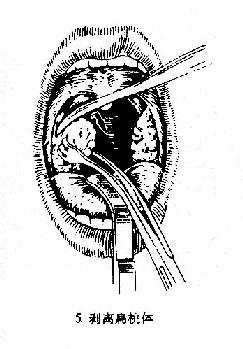

(一)剥离法(dissection method)(图6-2):

图6-2 扁桃体切除术(剥离法)

(2)剥离:用血管钳或剥离器插入舌腭弓切口,并向上后将扁桃体上极游离,然后用扁桃体钳夹持扁桃体上极,再以剥离器由上向下将扁桃体在其被膜外下周围组织分离,直至其下极。